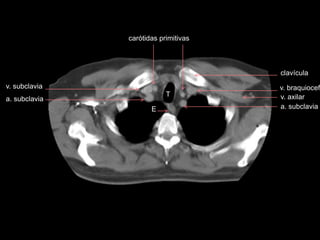

TOMOGRAFIA

carótidas primitivas

v. braquiocef.

a. subclavia

v. axilar

clavícula

v. braquiocef T a. subclavia v.subclavia v. axilar clavícula E a. subclavia carótidas primitivas

v. braquiocef. T E carótidas primitivas a.subclavia v. braquiocef. v. axilar clavícula